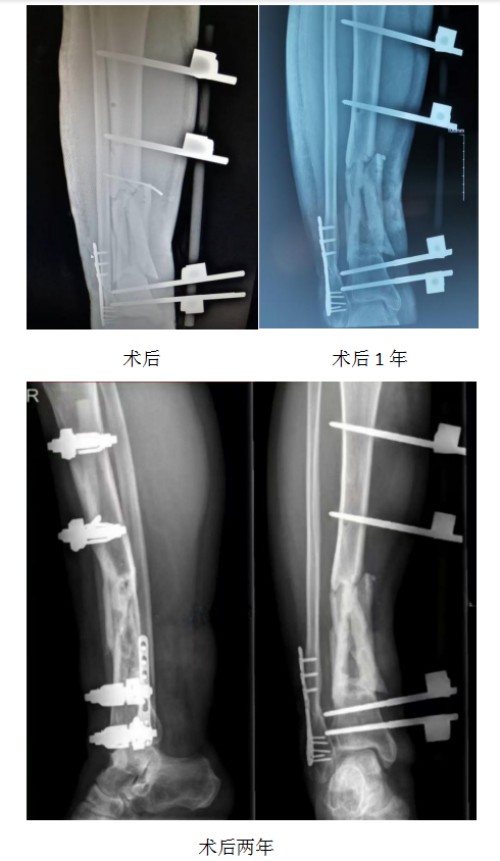

救治之路远比想象中艰难。第一阶段,国华为小伙子实施手术,通过外固定架固定骨折部位,让外露的骨面实现覆盖闭合,为后续治疗奠定基础;第二阶段,进行植皮手术,并对外固定架进行调整,特意解放踝关节,预防踝关节僵硬,为后续行走功能的恢复扫清障碍。然而,就在术后一年,新的难题出现了——骨折端迟迟不愈合,陷入了治疗瓶颈。

“当时患者家属都急坏了,想换大夫再试试,可跑了好几家医院均没有效手段。”国华回忆道,骨折端迟迟不愈合,他曾考虑采用内置钢板固定方案,但病人患处贴骨瘢痕,钢板根本无法顺利植入。面对无退路可走的绝境,他没有放弃,而是沉下心来深入研究骨传导力学原理,结合自己多年在骨科微创与固定技术上的积累,创新研究出“间断减压外固定架”技术,试图通过生物力学刺激促进骨愈合。

这是一场没有先例可循的尝试。为免患者往返奔波,国华通过电话指导患者配合操作:对固定骨折端的四个骨螺钉进行轮流松动、轮流放开,通过精准调控最大限度刺激骨折端骨应力。“过程很辛苦,孩子要一直配合调整,我也密切监测骨愈合情况,一点点摸索最佳方案。”国华说,功夫不负有心人,一段时间后,骨折端开始长出骨痂,希望的曙光终于出现。

随后,国华逐步调整治疗方案,将骨折端的四个骨螺钉逐步减少,最终仅保留各一个骨螺钉进行支撑,进一步加大骨折端的骨应力刺激,同时指导小伙子循序渐进进行康复训练——从借助双拐行走,到单拐辅助,再到最终摆脱拐杖独立行走,每一步都凝聚着医患双方的坚持与努力。更令人欣慰的是,在长达三年的治疗过程中,小伙子未发生任何骨髓炎等并发症,骨折端最终实现完全愈合。